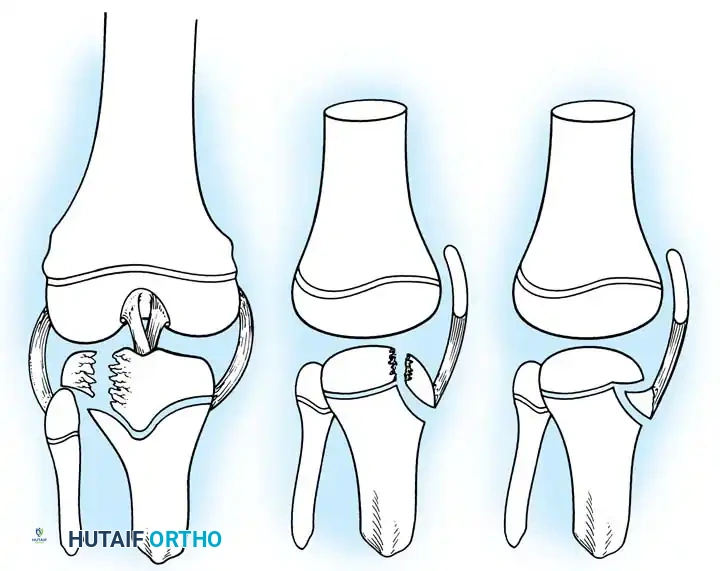

- Type III Fractures: These present in two distinct patterns:

- An intra-articular fracture analogous to an adult tibial plateau fracture.

- A fracture propagating through the tibial tuberosity physis, extending proximally across the epiphysis and into the knee joint.

Fig. 33-174: Salter-Harris type III fracture of the proximal tibia. A, Fracture analogous to a tibial plateau fracture. B, Fracture through the tibial tuberosity and across the epiphysis into the knee joint.

These tuberosity-extending fractures are not simple avulsions; they are massive, tongue-type Salter-Harris III injuries that lift the entire tibial tuberosity and anterior proximal physis superiorly. They almost universally necessitate open reduction and internal fixation (ORIF) to restore joint congruity and extensor mechanism continuity.

Fig. 33-175: Fixation of a tongue-type Salter-Harris III fracture utilizing cancellous screws.